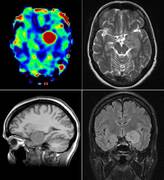

Arterial Spin Labeling - ASL

- Untersuchungen der Hirn-Perfusion bei den Patienten mit ischämischen Insulten ohne Applikation von Kontrastmittel.

- Differentialdiagnostik bei unklaren, zerebralen Raumforderungen.